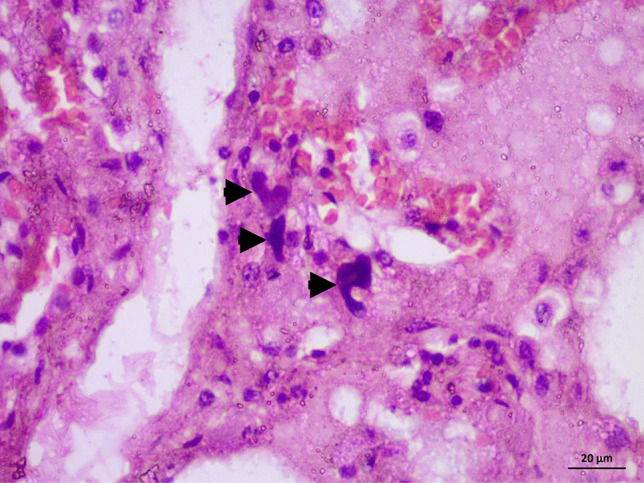

Case 4, a male in his 50s, died during renal surgery due to a complication of anesthesia. He exhibited facial congestion. A sutured lateral abdominal incision was observed. Renal sutures and a ureteric stent were also reported on gross examination. Histopathological examination of the brain revealed severe congestion. Figure 2 shows severe congestion, extravasation, edema, early neutrophilic, and entrapped megakaryocytes (Fig. 2), microscopic features of shock lung.

Fig. 2.

H&E-stained slides. (X400) for case 4: death during renal surgery, BME, and shock lung. Photo showing severe congestion, extravasation, edema, early neutrophilic, and entrapped megakaryocytes (arrow heads), microscopic features of shock lung